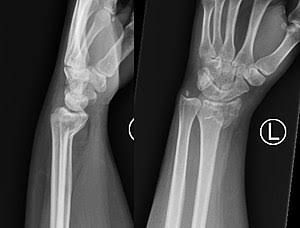

A Smith fracture is a break to the end of the radius. The end part of the bone, which forms part of the wrist joint, is displaced or angled in the direction of the palm of the hand. Often, this injury occurs by a fall to the back of a flexed wrist but can occur in any fall to an outstretched hand.